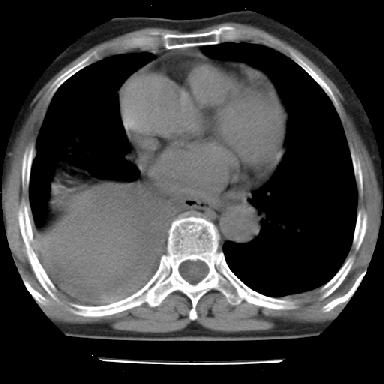

以下是引用苯小孩在2007-4-13 16:20:00的发言:[br]1、右下肺中央型肺癌并阻塞性肺不张、肺内转移、胸椎右侧附件亦有转移<横断层面第8层>.[br]2、右侧胸腔积液.

以下是引用swyyy2007在2007-4-13 15:31:00的发言:[br]右肺门下区肿块,右肺下叶支气管阻塞,右肺下叶不张,右侧大量胸腔积液,右肺中叶见结节状高密度影,边缘清,纵隔内见肿大淋巴结。首先考虑右下肺中心型肺癌伴右肺下叶不张、中叶、纵隔淋巴结转移。右侧胸腔积液。